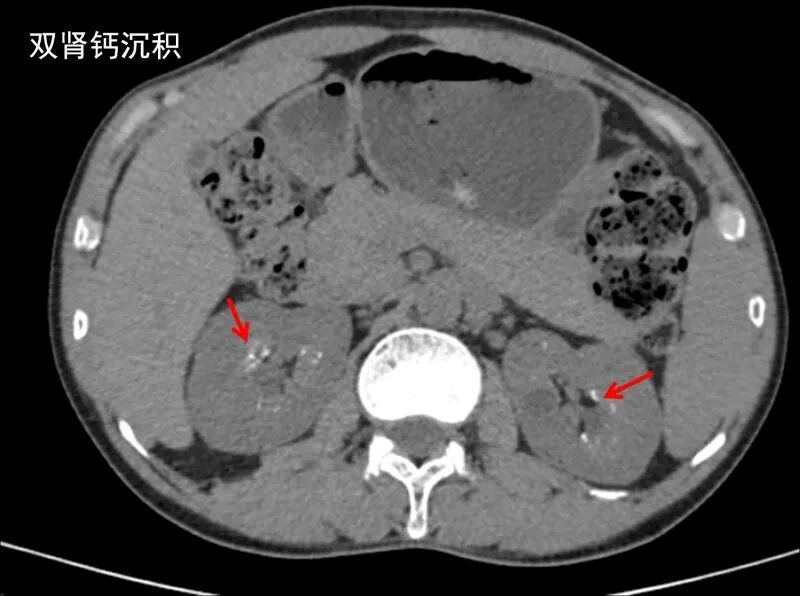

胸部CT可以查看到,部分上腹部可见双侧肾实质多发钙质沉着(图6),这是甲旁亢典型的肾脏表现。甲旁亢患者由于血钙升高和尿钙排泄增加,肾结石和肾钙质沉着的发生率明显增加,不明原因的肾结石、复发性或多发性肾结石应常规排除一下甲旁亢,一次血钙测定只需花5元钱,有可能早期发现甲旁亢。

图6.双肾实质泥沙样钙质沉着